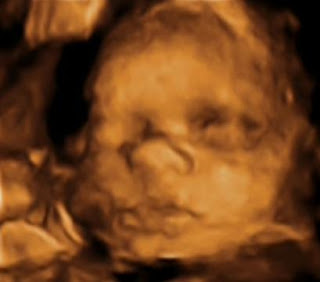

Eu sou a Clara!

Tenho 1,5 kg e quase 40 cm.

Já tenho cabelinho e já estou de cabeça pra baixo, só engordando e esperando a hora de sair…

Tenho duas bochechonas imeeeensas, que faz até um fundinho no meu rostinho.

Um narizinho igualzinho ao da mamãe.

E uma boquinha bem grandona.